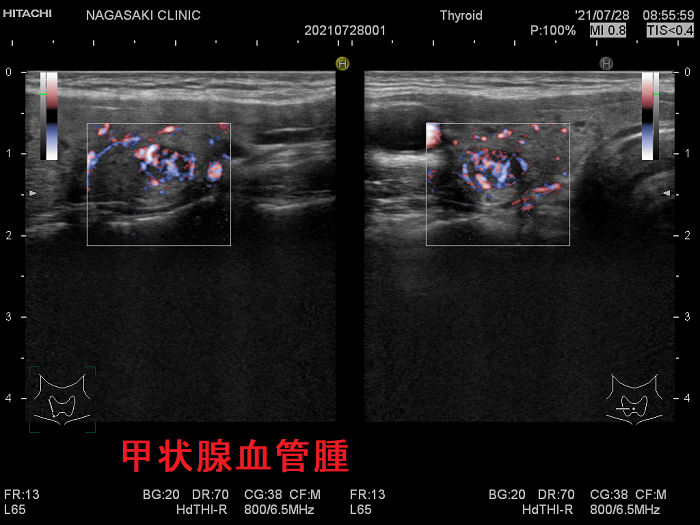

甲状腺に発生する血管腫は非常に稀で、日本の報告例もわずかです(日臨外会誌 72(3),579―583,2011)。

ケース①

ケース②

ケース③

甲状腺血管腫(拡大) ドプラーモード(eFlow);腫瘍内血管が3次元的に見え、毛玉の様。

ケース④